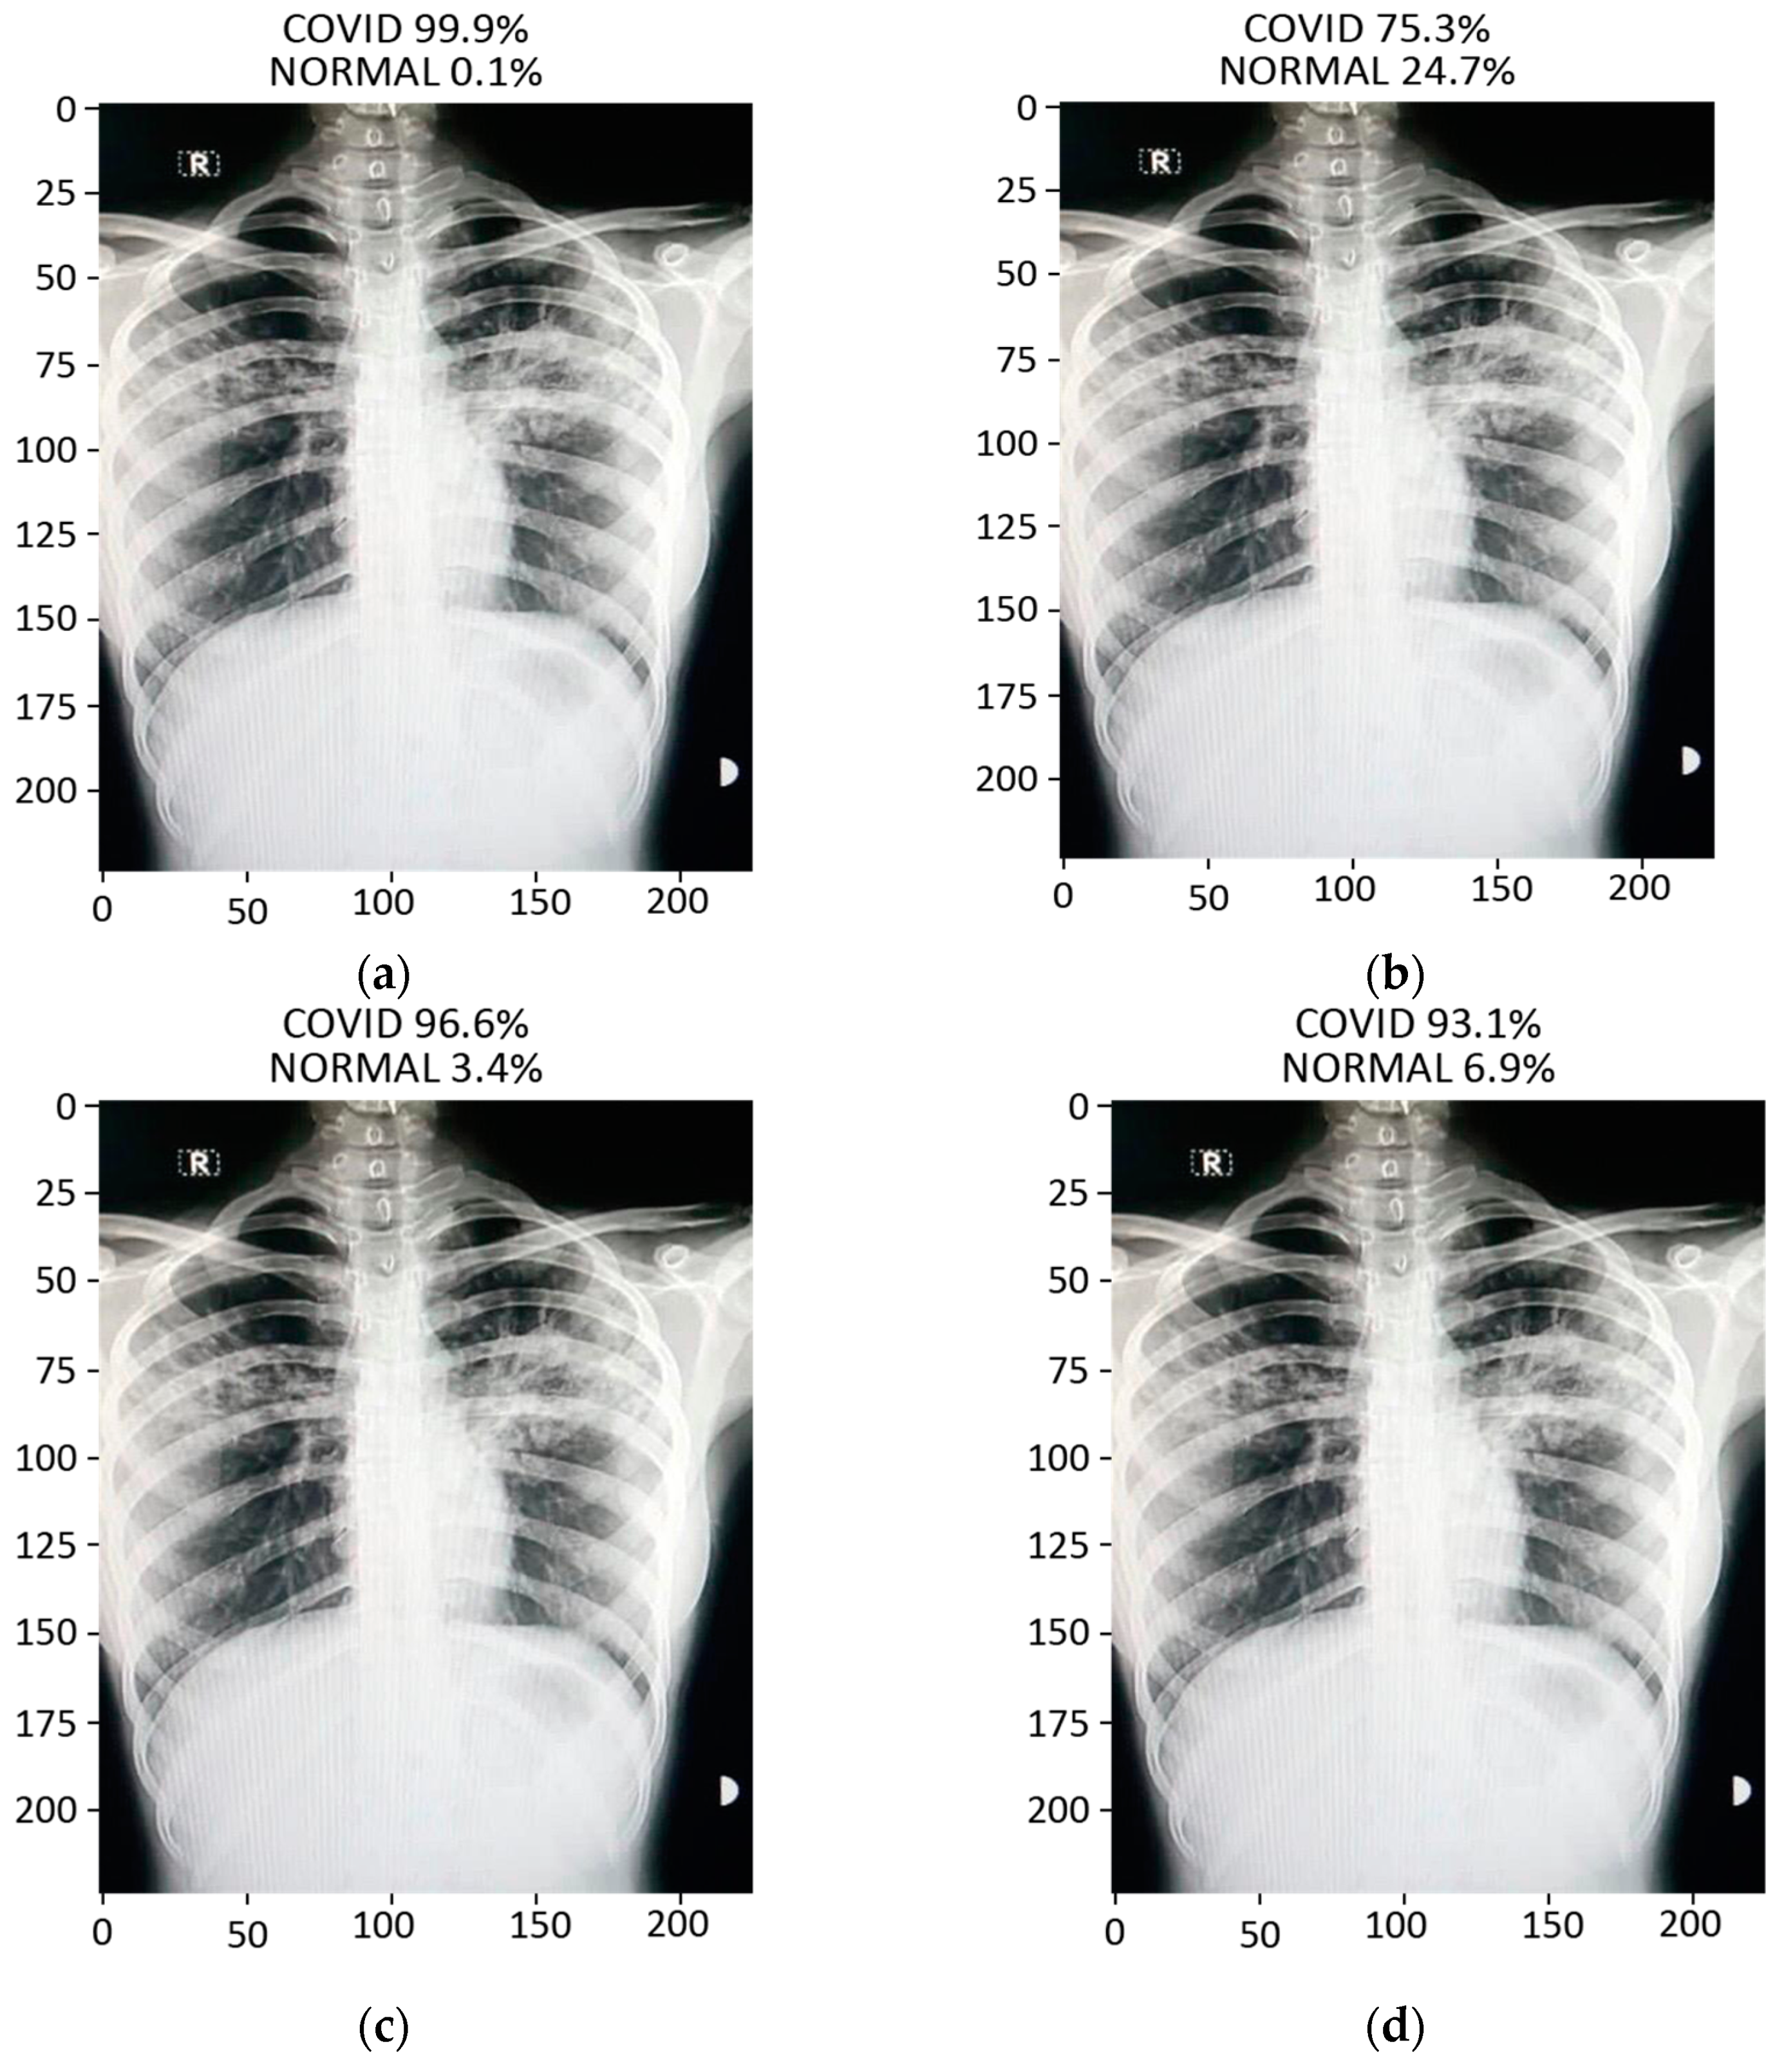

3.2.4. Prediction

The prediction result for a chest X-ray of a local COVID-19-positive patient for each model is given in Figure 13a–d. The DenseNet-121 had the highest probability percentage of COVID-19, i.e., 99.9%. In order to highlight the area where the model is paying the most attention during feature extraction, the Grad-CAM technique was applied. The Grad-CAM results of all four models under study are given in Figure 14. Moreover, the results of the predicted normal patients for each model are shown in Figure 15a–d. Considering these results, the MobileNet has the highest probability of 96.8% for the prediction of a normal chest X-ray.

Figure 13.

Results of prediction on a verified local Pakistani COVID-19 chest X-ray: (a) DenseNet-121; (b) VGG16; (c) MobileNet; (d) ResNet-50.